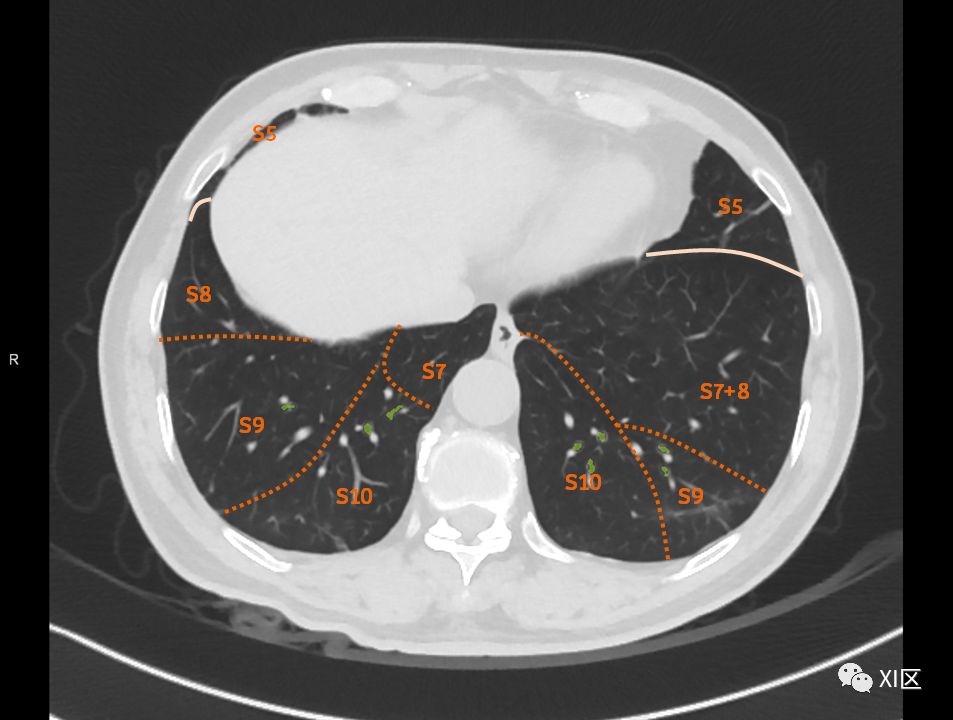

在进行肺的分段时,可以上下观察浏览,沿着相应气管的走形可以更容易准确地进行分段。

肺的断层分段示意图